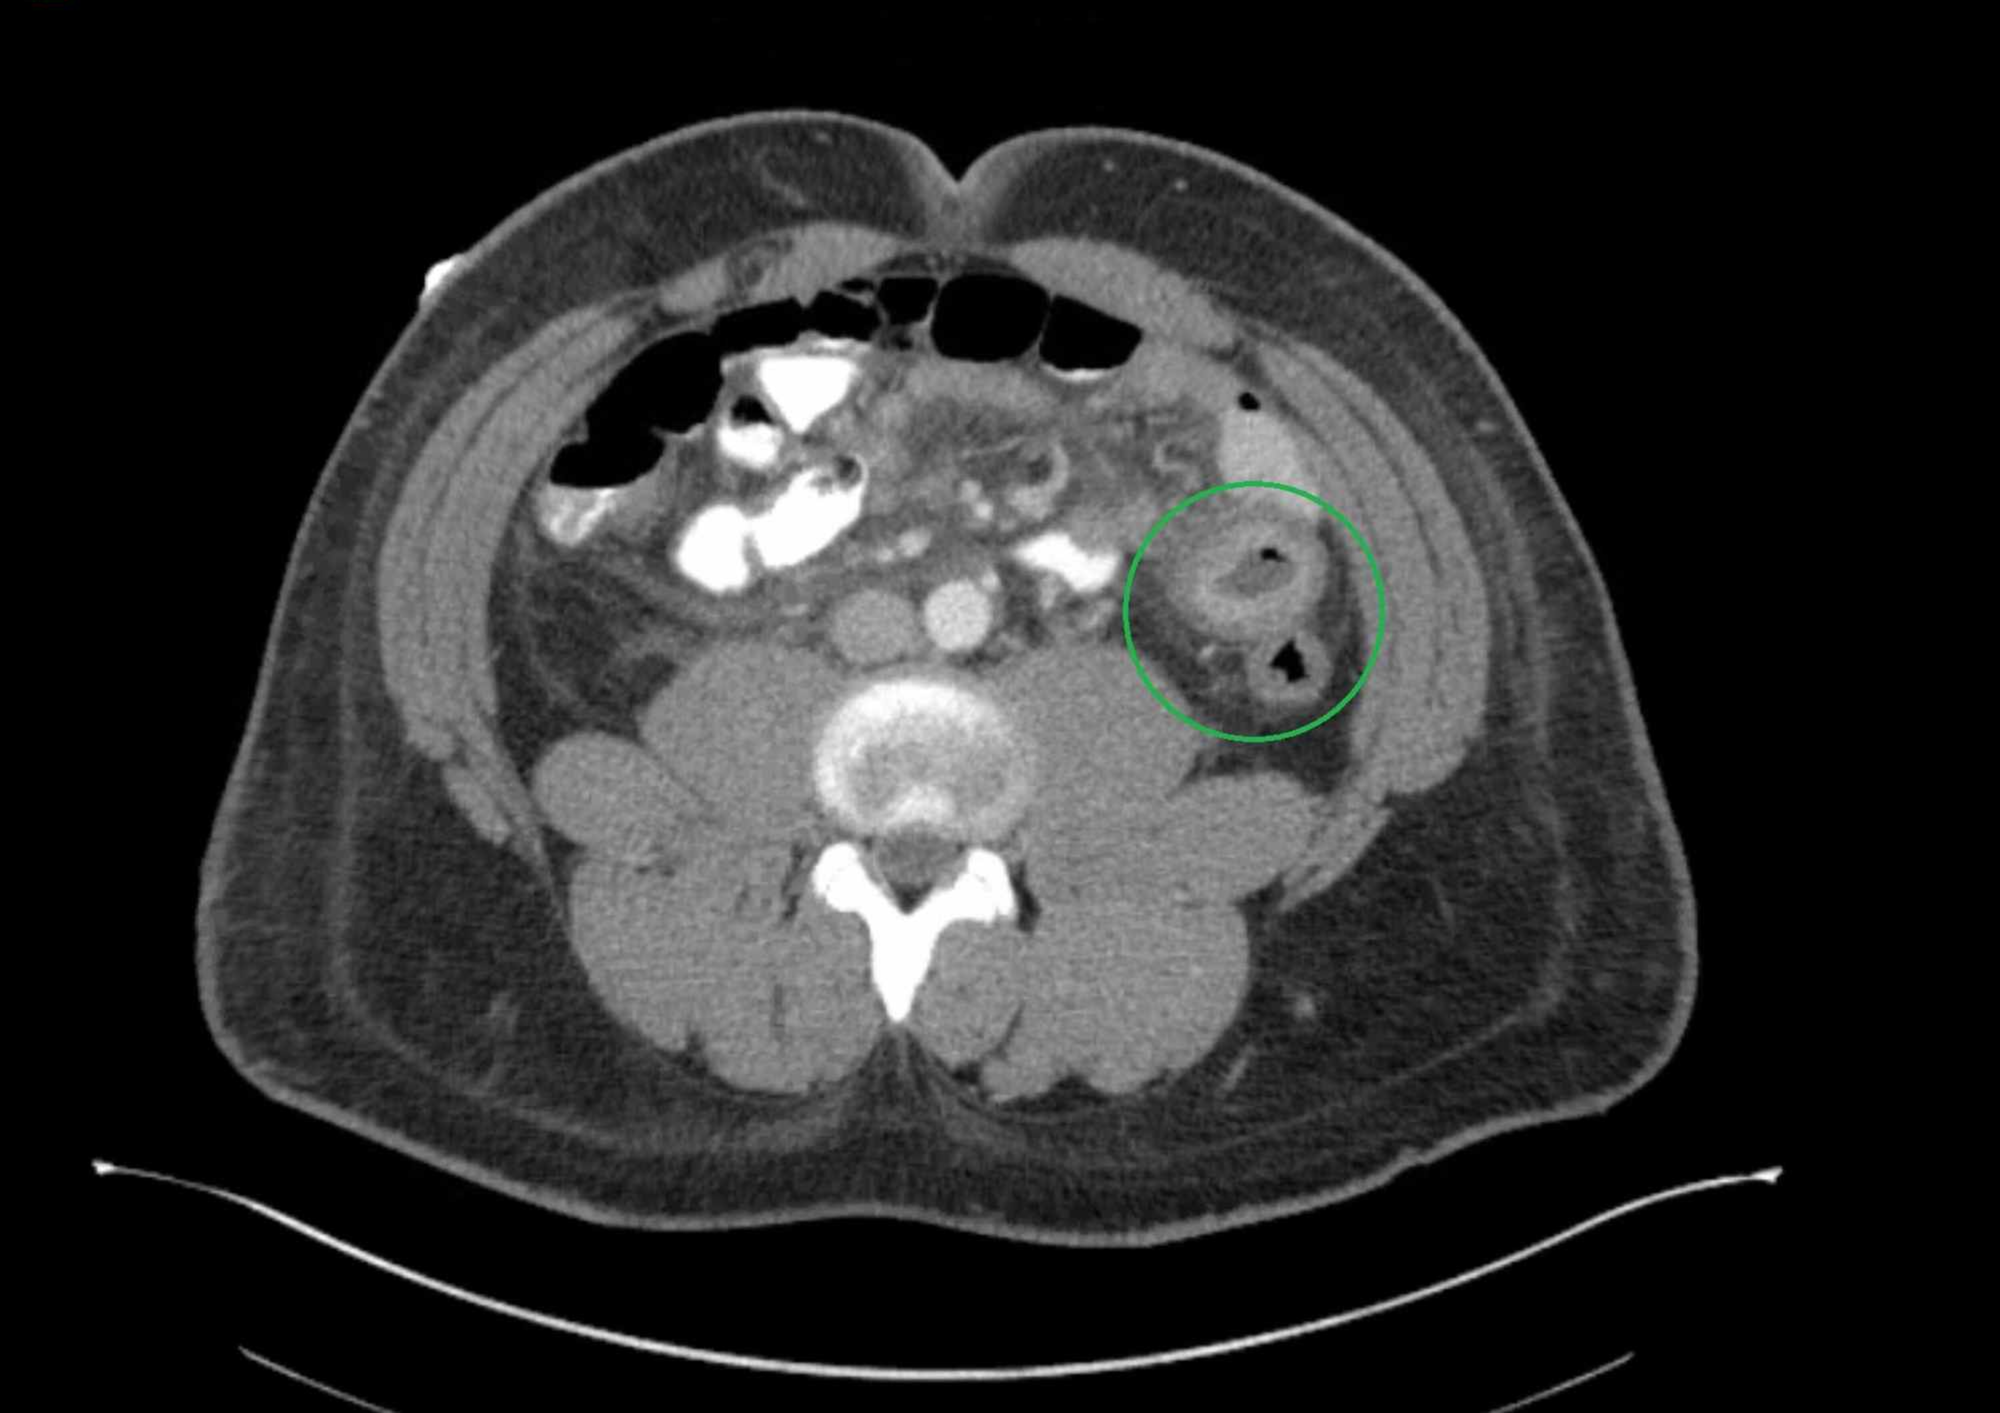

Axial view of CT abdomen showing comb sign. Download Scientific Diagram Comb Sign Radiology The comb sign refers to the hypervascular appearance of the mesentery in active crohn disease. The comb sign is a ct feature of parallel engorged mesenteric vessels supplying inflamed bowel segments in crohn's disease. Here is a case with typical ct findings of crohn disease including the comb sign. Computed tomography and magnetic resonance enterography have become routine small bowel. Comb Sign Radiology.